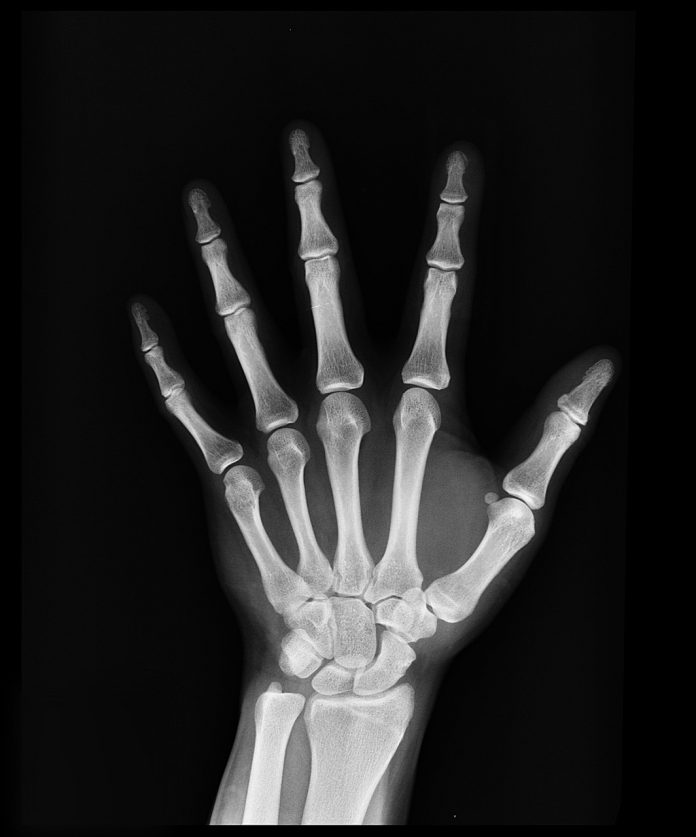

ขึ้นชื่อว่าเป็นมะเร็งกระดูกมั่นใจว่าต้องไม่มีใครอยากจะเป็นหรือสัมผัสมันสักเท่าไรนักเพราะแค่มะเร็งโดยทั่วไปก็ถือว่าร้ายแรงแล้วยิ่งไปเกิดขึ้นที่กระดูกด้วยละก็รับรองได้เลยว่าไม่สนุกอย่างที่คิดแน่ๆเพราะร่างกายของมนุษย์เรานั้นโดยทั่วไปแล้วจะประกอบไปด้วยกระดูกเป็นโครงสร้างหลักเพื่อที่จะทำหน้าที่ให้ที่ยึดติดแก่กล้ามเนื้อและผิวหนังของคนเรามากถึงแปดสิบเปอร์เซ็นดังนั้นกระดูกจึงจัดว่าเป็นอวัยวะที่สำคัญอย่างมากของร่างกายถ้าไม่มีกระดูกเราก็ไม่สามารถที่จะยืนหรือทรงตัวได้นั้นเองแต่ถ้าหากว่าความโชคร้ายนั้นได้มีขึ้นกับเราแล้วเราจะมีวิธีตั้งรับหรือจัดการกับมันเช่นใดตามหลักแล้วการเกิดมะเร็งกระดูกนั้นไม่ได้อยู่ดีๆจะเกิดขึ้นมาได้เองแต่ต้องเกิดจากความผิดปกติของเม็ดโลหิตบางชนิดในโพรงไขกระดูกหรือเกิดจากเซลของมะเร็งจากส่วนอื่นแล้วลามไปยังกระดูกซึ่งถ้าหากว่าลามไปถึงแล้วก็คงยากต่อการดูแลรักษาแต่เราจะมีวิธีการป้องกันตัวเองอย่างไรไม่ไห้เกิดมะเร็งกระดูกกับเราได้เริ่มจากการรับประทานอาหารให้ครบทั้งห้าหมู่ดูแลดูแลรักษาร่างกายให้แข็งแรงอยู่เรียบและพยายามตรวจสุขภาพหรือตรวจร่างกายอยู่เป็นประจำถ้าพบสิ่งเพี้ยนจากที่เป็นอยู่ก็ควรรีบปรึกษาแพทย์ทันทีทันใดเพื่อที่เราจะได้รู้และรับมือกับ